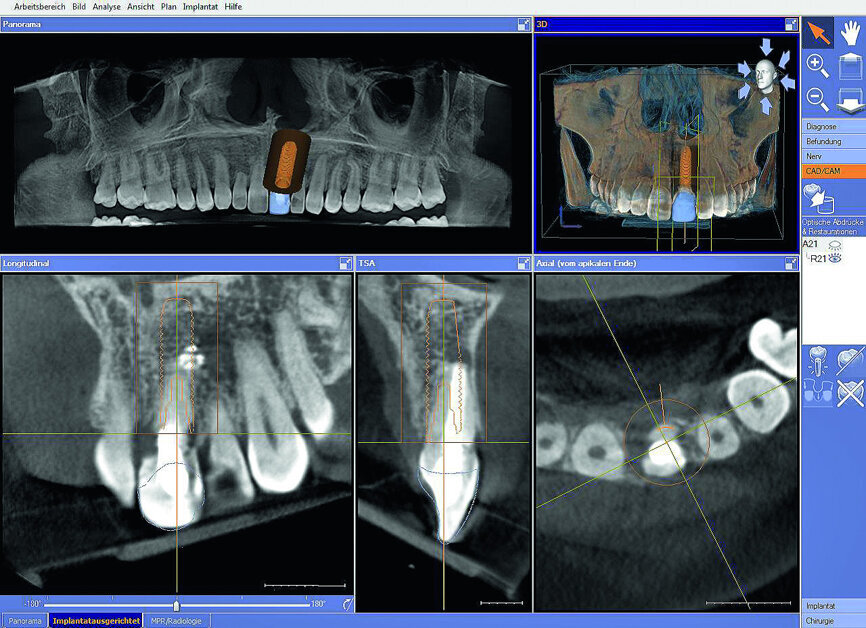

Fig. 3: The initial situation in 3-D in the Sidexis 4

imaging software (Dentsply Sirona) showed good apical bone substance with the possibility of immediate implantation.

Fig. 4: Tooth #21 was deleted in CEREC to simulate the initial post-op situation.

Fig. 5: The prosthetic proposal was also used as the basic file for producing the surgical guide with the gap at position #21.

Fig. 6: The intraoral CEREC scan superimposed over 3-D image data for optimal positioning of the implant in the Galileos Implant planning software.

The female patient, born in 1989, came to my practice with problems at tooth #21 caused by a childhood trauma. The gingival margins were reddened and bled when probed. The intraoral radiograph showed posttraumatic resorption of the root, and the tooth could therefore not be preserved (Figs. 1 & 2). The tooth was to be replaced by an implant with an all-ceramic crown immediately after extraction. To plan the procedure, a 3-D radiograph (Orthophos XG 3D, Dentsply Sirona) was taken. It was important to assess the available horizontal and vertical bone and evaluate apical osteolytic processes after the failure of endodontic treatment and in the region of the crestal bone due to progressive dentinal resorption. The integrity of the vestibular lamina was preserved, and there was sufficient apical bone to allow immediate implantation with immediate loading (Fig. 3).

After scanning the upper jaw, tooth #21 was deleted in CEREC to simulate the initial postoperative situation. The prosthetic proposal for tooth #21 was used to optimise implant planning and to produce the surgical guide (Figs. 4 & 5). In the implant planning software (Galileos Implant, Dentsply Sirona), the prosthetic proposal was superimposed over the CBCT data for the optimal positioning of the implant. In this way, sufficient vestibular distance was ensured, and the correct size of the implant for optimal primary stability could be selected (Fig. 6).